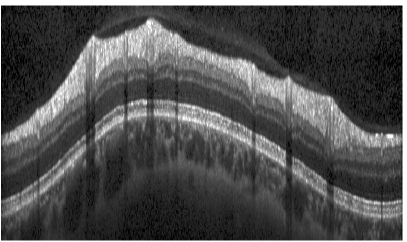

6.2 Volumetric Scans

In contrast to 2-D scans, the labeling of OCT volumes is very time consuming, hence our data set only consisted of 35 samples. Thus we were left with less data points to train a shape model of much higher dimension. Consequently, we observed a reduced ability of p(b)𝑝𝑏p(b) respectively qb(b)subscript𝑞𝑏𝑏q_{b}(b) to generalize well to unseen scans. We tackled this problem by reducing the dimensionality of p(b)𝑝𝑏p(b) and by interpolating it for intermediate columns, which fixed the problem only to some extent.

We further pursued this idea and suppressed the connectivity between different B-scans, which corresponds to a block-diagonal covariance matrix ΣΣ\Sigma, where each block is obtained separately using PPCA. This significantly reduced the amount of parameters that had to be determined, and improved accuracy significantly. The last column in Table 2 reports results for all boundaries.

The average segmentation error of 2.46μm2.46𝜇𝑚2.46\,\mu m is significantly smaller than for circular scans, as well as the standard deviation of 0.22μm0.22𝜇𝑚0.22\,\mu m. Reasons are smoother boundary shapes and less severe texture artifacts caused by e.g. blood vessels. Representative for the average segmentation performance, Fig. 14 shows B-scans of the same volume from four different regions, with an error of 2.53μm2.53𝜇𝑚2.53\,\mu m averaged over the all scans in the volume.

Refer to caption

(a)

(b)

(c)

(d)

(e)

(f)

(g)

(h)

Figure 14: Four segmented B-Scans from regions 2, 6, 9 and 11 of the same volume (Eunsgn=2.53μmsubscript𝐸unsgn2.53𝜇𝑚E_{\mathrm{unsgn}}=2.53\,\mu m).